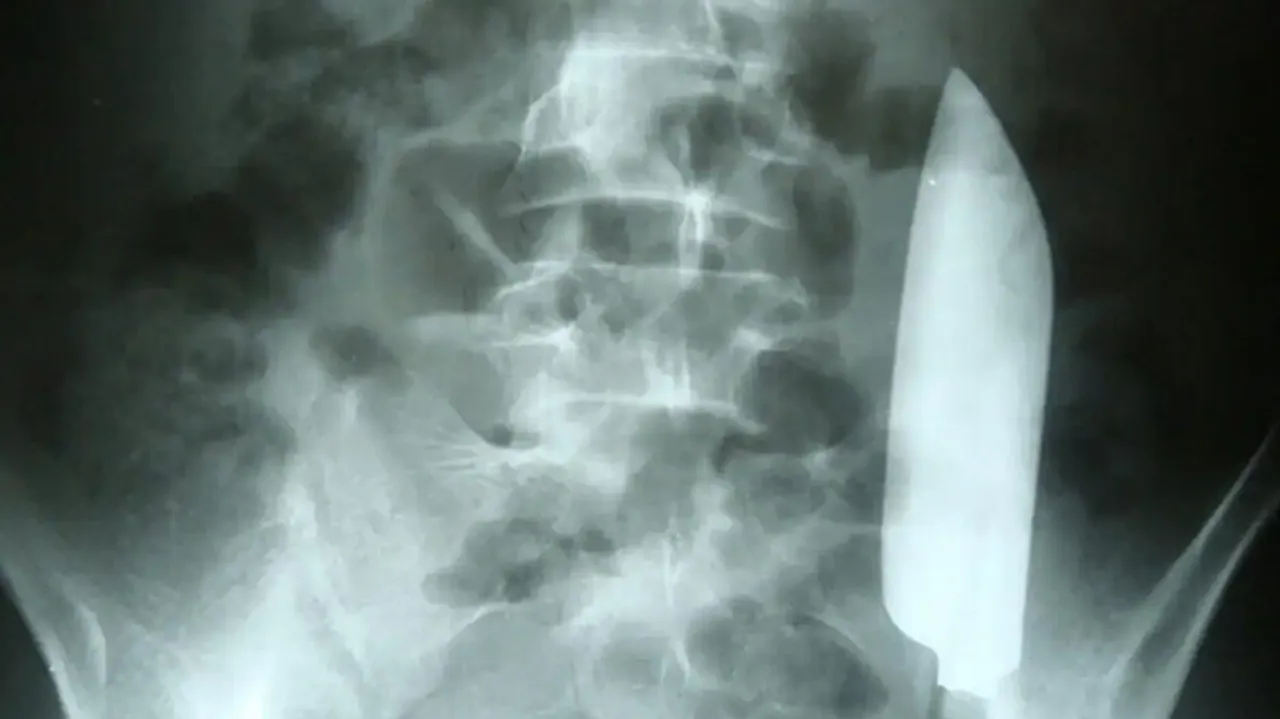

ପେଟ ଯନ୍ତ୍ରଣାରେ ଛଟପଟ ହେଉଥିବା ନେପାଳର ଜଣେ ୨୨ ବର୍ଷୀୟ ଯୁବକଙ୍କ ସହ ଘଟିଛି ଅଜବ ଘଟଣା। ସେ ପେଟ ଯନ୍ତ୍ରଣା ଯୋଗୁ ହସ୍ପିଟାଲ ଯାଇଥିଲେ। ଯାଞ୍ଚ ବେଳେ ତାଙ୍କ ତଳି ପେଟରେ ୧୫ ସେମିର ଗୋଟିଏ ଛୁରୀର ବ୍ଲେଡ ରହି ଯାଇଥିବା ଜଣାପଡ଼ିବା ପରେ ସମସ୍ତେ ଚକିତ ହୋଇଛନ୍ତି।

ଏକ୍ସ ରେରୁ ଜଣାପଡ଼ିଥିଲା ଯେ ଯୁବକଙ୍କ ତଳି ପେଟରେ ୧୫ ସେମିର ଛୁରୀର ବ୍ଲେଡ ରହି ଯାଇଛି। ଛୁରୀଟି ଗୋଟିଏ ପଟରୁ ଆଉ ଗୋଟିଏ ପଟୁ ମଧ୍ୟ ଘୁରି ବୁଲୁଥିଲା। ତେବେ ଏହା ଦ୍ୱାରା ତାଙ୍କ ଶରୀର କୌଣସି ଅଙ୍ଗ ଗୁରୁତର ଭାବେ କ୍ଷତିଗ୍ରସ୍ତ ହୋଇ ନାହିଁ। ଏକଥା ଜଣାପଡ଼ିବା ପରେ ଡାକ୍ତରମାନେ ସର୍ଜରୀ ପରେ ଛୁରୀଟିକୁ ତାଙ୍କ ପେଟରୁ କାଢ଼ି ଦେଇଛନ୍ତି।